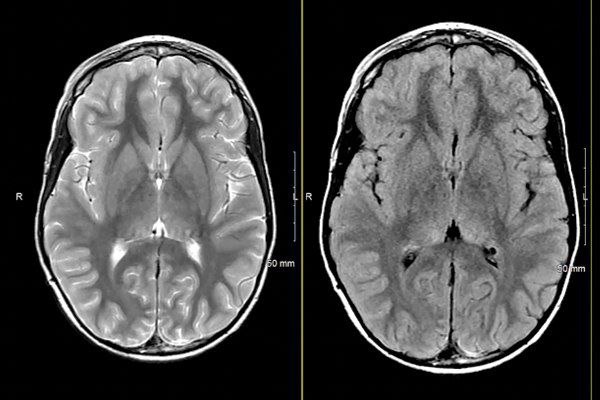

- NF1 with Developing Myelin Vacuolization, and Optic Glioma

- Normal Brain MRI in Patients with NF1